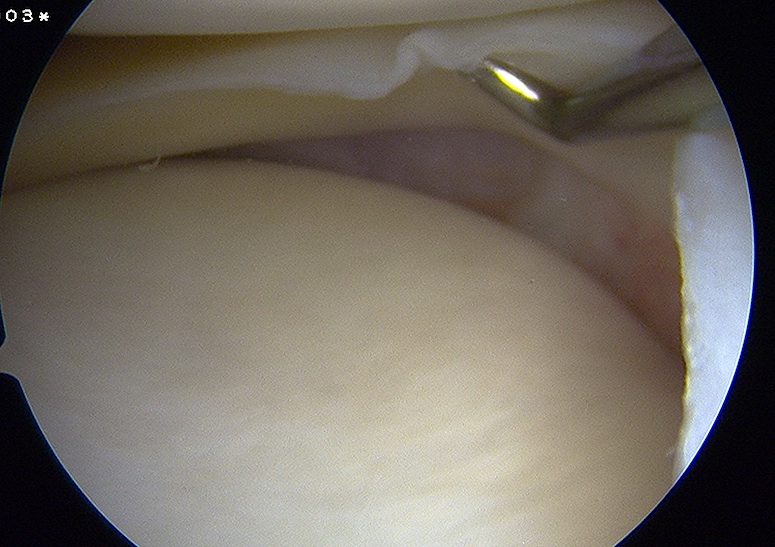

Arthroscopy

Findings

- medial drive through sign

- excessive opening of medial compartment

- may see lift off of the medial meniscus with injury to deep MCL / meniscotibial ligament

- may see injury above medial medial meniscus with injury to deep MCL / meniscofemoral ligament

Meniscotibial ligament injury Meniscofemoral ligament injury